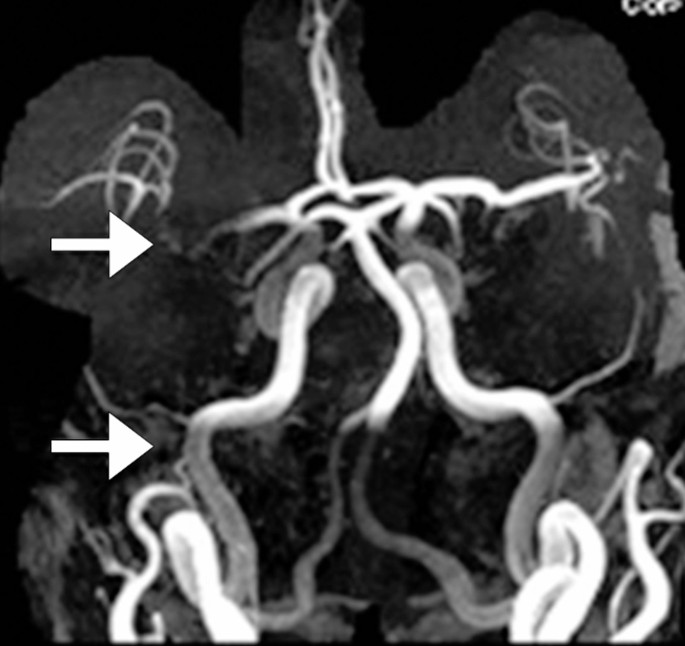

- MRI 可提供腦部及其血管的詳細影像,從而評估中風類型。

- MRI 亦可顯示缺血性中風時血管阻塞的部位和範圍,或出血性中風時出血的部位和範圍,從而提供選擇合適治療方案的指導。